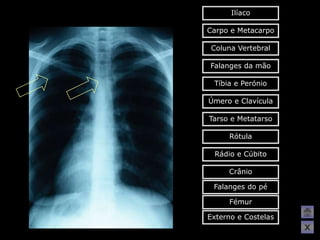

Ilíaco Carpo e Metacarpo Coluna Vertebral Falanges da mão Tíbia e Perónio Úmero e Clavícula Tarso e Metatarso Rótula Rádio e Cúbito Crânio Falanges do pé Fémur Externo e Costelas X